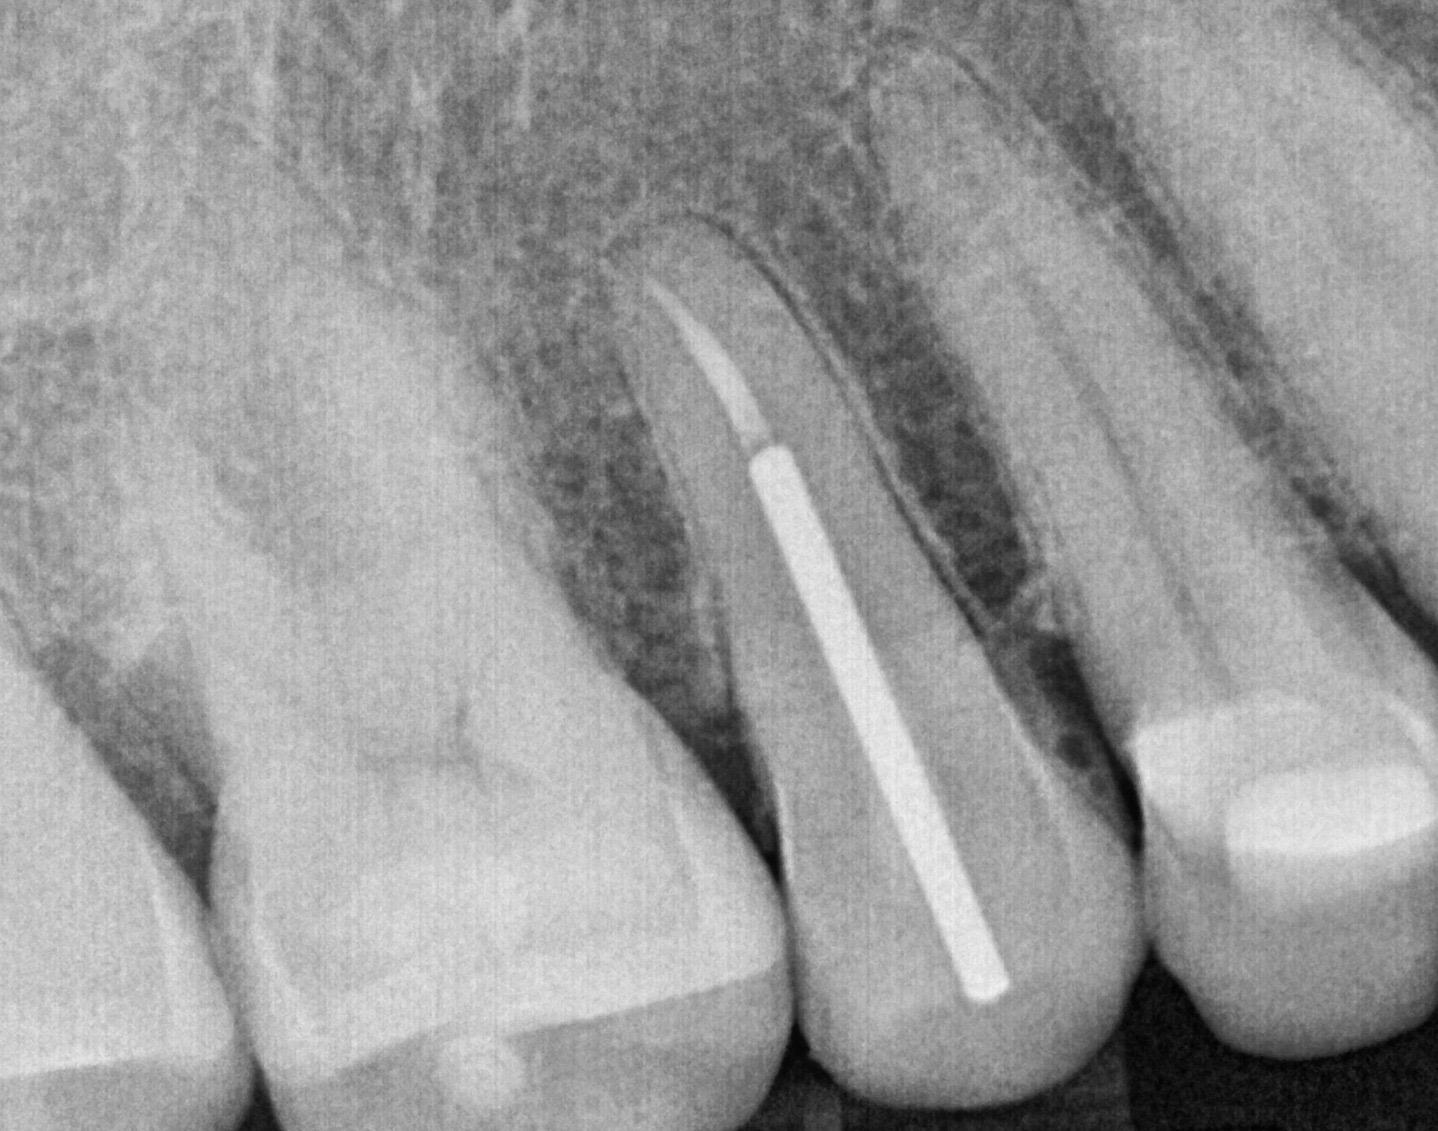

Access Cavity Prep

What we did:

● Cleaned and shaped two canals

● Removed infected and inflamed tissue

● Filled the tooth with gutta-percha and bioceramic sealer

Obturation & Post Placement #4

● Placed a post and core as requested by the referring dentist

Post placement